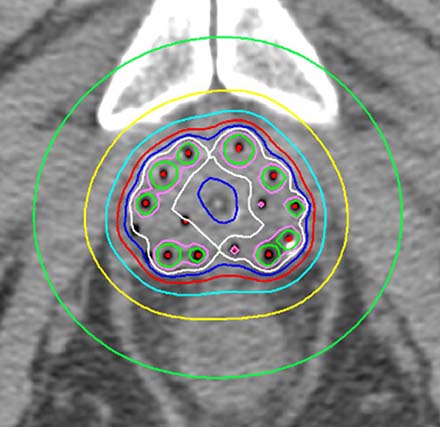

高線量率組織内照射法は、前立腺内に針を挿入し、放射線を放出するイリジウム192線源(直径0.9mm)をその針の内腔に一時的に停留させることで、短い時間でたくさんの放射線をあてる治療法です。線源の位置およびその停留時間を変化させることにより自由な線量分布を作成することができるため、尿道、直腸や膀胱などの線量を最小限にし、病巣(前立腺や精嚢)に対して十分な放射線をあてられることがこの治療法の利点です。

治療当日は、全身麻酔を行い前立腺に針を挿入します。針を挿入後に治療計画CTを撮像し、MRI画像をもとに患者さん一人ひとりにあった治療計画を立案します。さらに、尿道や直腸、膀胱にできるだけ放射線が当たらないように治療計画を立案し、正常臓器への被ばくを最小限にしながら、腫瘍に対して高線量を投与するように努めています。治療にかかる時間は約3時間程度です。